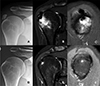

Of the 19 Type III cases with bone involvement, twelve were classified as Type III-a (cortical erosion without intraosseous extension) (Figure 3), six as Type III-b (intraosseous extension through a cortical breach) (Figure 4), and one as Type III-c (deep medullary involvement) (Figure 5). The “hourglass sign”, indicating continuity between the tendon deposit and intraosseous component, was observed in 83% of Type III-b cases (Figure 4C).

Figure 3 Magnetic resonance imaging of a Type III-a calcification in the subscapularis tendon. A. Axial view showing a calcific deposit in direct contact with the cortex of the lesser tuberosity, associated with marked subcoracoid bursitis. B. Oblique sagittal view demonstrating focal cortical erosion at the site of contact (black arrow), without evidence of intraosseous extension. |

Figure 4 Advanced intraosseous migration (Type III-b) of a supraspinatus calcification with spontaneous resolution at follow-up. A. Initial anteroposterior (AP) radiograph showing the calcific deposit. B. Coronal MRI revealing intraosseous extension of the deposit with associated bone marrow edema. C. Oblique sagittal MRI demonstrating the “hourglass sign,” indicating tendon-to-bone continuity. D. Follow-up AP radiograph two years later showing complete disappearance of the calcification. E. Coronal MRI confirming resolution of the intraosseous deposit. F. Oblique sagittal MRI showing complete resolution of both the calcification and bone marrow edema. |